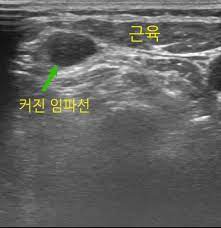

이 미네랄은 고기, 생선, 조개류, 가금류 및 콩에서 발견됩니다. 건강하게 먹으면 신체가 정상적으로 기능하는 데 필요한 구성 요소를 갖게 됩니다. 면역 체계의 기능을 저하시키는 음식도 피해야 합니다. 림프절은 신체의 주요 방어 시스템인 림프절의 세균 감염으로 인해 발생합니다. 따라서 면역 체계의 기능을 저하시키는 음식을 피하는 것이 중요합니다. 여기에는 몸을 식히는 각얼음이 포함됩니다. 염증을 촉진하는 지방 음식; 혈관을 열어주는 매운 음식; 배설 시스템을 막는 기름진 음식; 해로운 박테리아를 먹이는 단 음식; 그리고 혈류량을 손상시키는 알코올음료. 따라서 매일 레몬주스를 마시면 머릿니와 비듬을 예방할 수 있습니다. 레몬을 반으로 자른 후 과즙을 컵에 짜서 물이나 설탕을 섞지 않고 그대로 드세요!

레몬주스에는 헬리코박터 파일로리(궤양의 원인)를 비롯한 소화 시스템의 해로운 박테리아를 죽이는 천연 항균 특성이 있습니다. 또한 혈류를 증가시키는 혈액 정화 특성이 있어 혈액이 불순물을 제거하고 건강한 식습관과 같은 수준으로 면역 체계를 강화합니다! 림프절염은 림프절의 박테리아 감염으로 인한 질병입니다- 신체의 주요 방어 시스템.. 깨끗한 환경을 유지하고 좋은 음식은 질병을 예방합니다. 또한 매일 레몬주스를 마시는 것도 피해야 합니다. 이렇게 하면 머릿니와 비듬을 예방할 수 있습니다.. 깨끗한 환경을 유지하면 질병을 예방할 수 있습니다. 날씨 아래 느낄 때 마음!